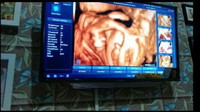

Hasil USG 4D

Hemzz..bunda jg usg yg 4D ya..

Hhe iya bund.. monas jelas bgt

Iya bun,awalnya usg mau liat kesehatan dedek sama posisi plasenta,alhamdulilah jk dedek udah kelihatan